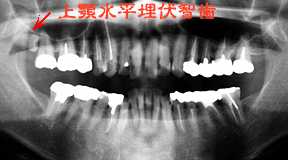

有りそうで珍しい、上顎水平埋伏智歯!!

初診時 パノラマ 最近話題の猿人

上顎親知らずは症状なし

口腔清掃状態は比較的良好であったが、年齢の割にカリエスおよび歯冠補綴は著明であった。 エックス線所見で目をひいたのが、右側上顎の水平埋伏智歯であった。臨床症状はなく、現状では 抜歯の必要はないものと判断。

智歯の存在意義とか抜歯の可否について問題になることが多いようですが、歯肉、または顎骨 内に完全埋伏した状態で臨床症状の全くないものは抜歯の対象になることはありません。 人類の進化過程において、20歳前後に遅れて萌出する智歯は別名第三大臼歯とも呼ばれ 文字通り第三の歯として活躍したものと思われます。直立歩行が可能となり、骨格系の変化 によりアゴの形と大きさが変ったことにより萌出余地の減少で正常方向への萌出が困難に なったことが伺われます。

下顎の智歯は近心傾斜が多く、“水平埋伏智歯”になる可能性が高いようですが、上顎の智歯 は遠心または頬側方向への傾斜傾向が強いので“水平埋伏智歯”となるのが比較的稀なこと と思います。 私自身20年間の臨床経験の中で、これほど見事な“上顎水平埋伏智歯”を見たのはおそらく 初めてです。

“アウストラロピテクス・ガルヒ”の新聞発表の日だったので、思わず感激!!